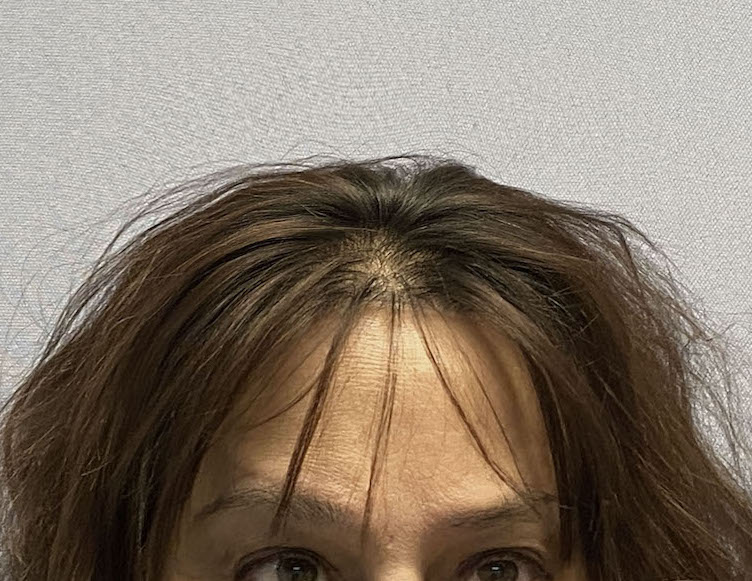

Patient 45

Desire for reduction in height of top of head.

Top of head skull reduction by removal of the outer cortical bone layered by a grid burring technique.

Desire for reduction in height of top of head.

Top of head skull reduction by removal of the outer cortical bone layered by a grid burring technique.